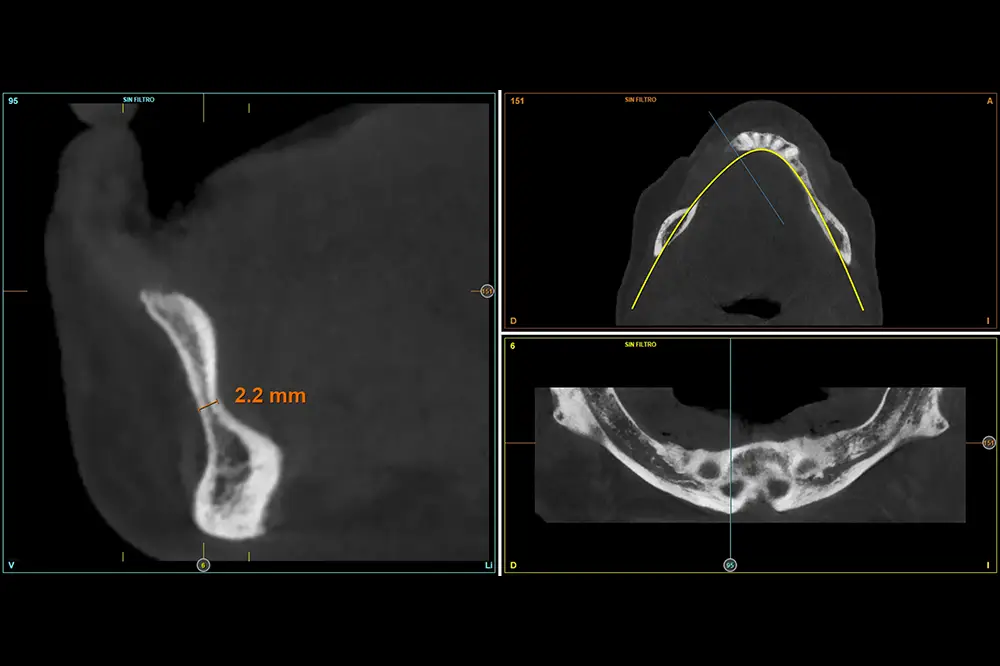

Figuras 8-11. Cortes seccionales del cone-beam de planificación del tercer cuadrante, donde podemos observar la extrema atrofia horizontal que encontramos en algunas localizaciones, con menos de 4 mm de anchura. Por ello, se planifican implantes de 2,5 mm en todo el cuadrante.